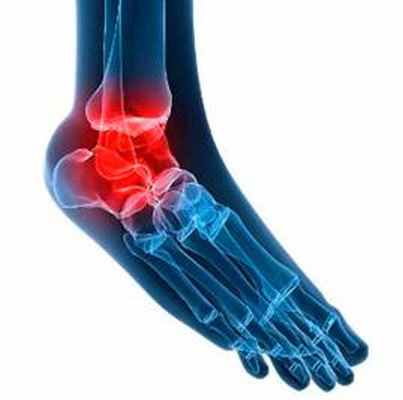

Голеностопный сустав обладает большой двигательной активностью, он устойчив и функционален. Такие превосходные характеристики голеностоп имеет за счёт большого количества суставных поверхностей, он обладает сложным анатомическим строением и окружён многочисленными мышцами и сухожилиями. Однако даже такая идеальная с виду система может давать сбои [1]. Что такое остеоартроз голеностопного сустава, его причины, симптомы, лечение и многое другое подробно разбираем в статье.

Что такое остеоартроз голеностопного сустава

Остеоартроз голеностопного сустава (или артроз, деформирующий остеоартроз, крузартроз [2]) — дегенеративное заболевание, при котором постепенно разрушается суставной хрящ и окружающие ткани голеностопного сустава [1]. Разрушенный хрящ затрудняет скольжение суставных поверхностей [3], суставная щель сужается [4]. Это приводит к появлению болей, чувства скованности, тугоподвижности, быстрого утомления, деформации сустава [2]. Частота остеоартроза голеностопного сустава составляет до 25% от всех случаев остеоартроза [4].

При нарушении функции хондроцитов или их гибели выработка хрящевого матрикса становится неполноценной. Хрящ разволокняется, с трудом удерживает воду [5], становится шероховатым, в нём образуются трещины, происходит обнажение кости [6]. Голеностопный сустав несёт самую большую нагрузку среди остальных суставов [3]. Отсутствие амортизации при давлении на суставную поверхность костей приводит к их уплотнению, нарушению кровоснабжения, появлению кист. Одновременно по краям суставных поверхностей неполноценный хрящ компенсаторно разрастается, происходит окостенение его участков (появляются остеофиты), что ещё больше нарушает подвижность и деформирует сустав. При этом в патологический процесс вовлекаются соседние суставы стопы: надтаранный и подтаранный [6].